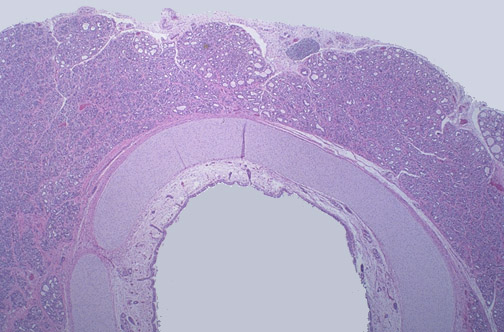

The normal fetal thyroid gland reveals the relationship of the thyroid anterior to the tracheal cartilage in the neck.